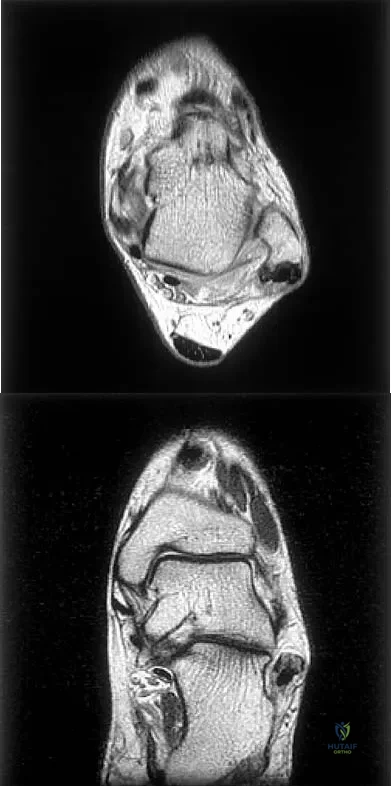

Figures 5a and 5b show axial and coronal MRI images of the left ankle of a patient with lateral ankle pain. What is the most likely diagnosis?

Explanation